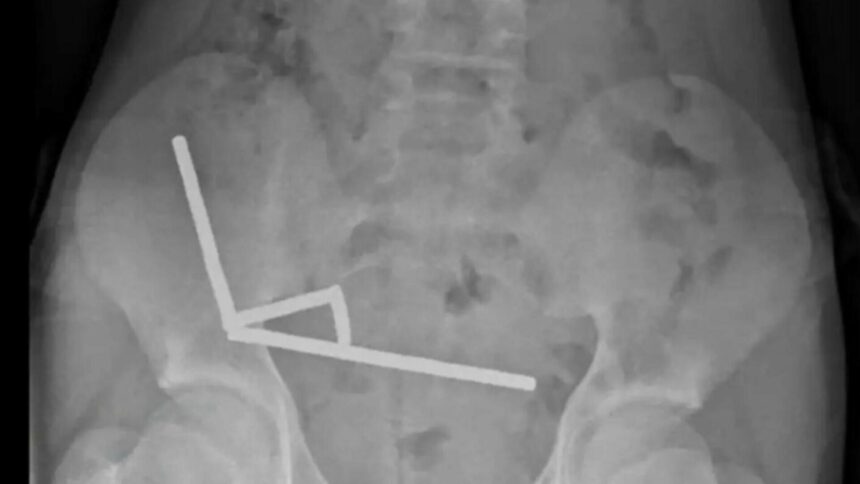

Inițial, adolescentul a declarat că a înghițit între 80 și 100 de magneți, dar intervenția chirurgicală a relevat că numărul real era aproape dublu. Imaginile radiologice au arătat patru lanțuri magnetice prinse în intestin, blocând circulația sângelui și provocând necroză intestinală. Medicii au fost nevoiți să îndepărteze o porțiune din intestin pentru a-i salva viața.